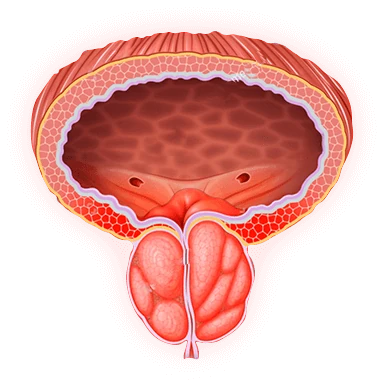

¿Cómo funciona Prostalis en la práctica?

Aunque el fabricante no detalla un mecanismo exacto, podemos inferir el método de acción a partir de los componentes. La Serenoa actúa sobre los receptores de dihidrotestosterona (DHT) en la próstata, reduciendo la estimulación hormonal que favorece el crecimiento de tejido prostático. La equinácea potencia la respuesta inmune, lo que ayuda a controlar cualquier proceso inflamatorio que pueda estar presente. El Ginkgo, al dilatar los vasos sanguíneos, facilita la llegada de oxígeno y nutrientes al tejido prostático y al pene, lo que se traduce en una mejor función eréctil. El licopeno, al neutralizar los radicales libres, protege las células de mutaciones potencialmente cancerígenas, mientras que el zinc asegura que la producción de testosterona sea óptima, manteniendo la libido y la salud reproductiva.

- •La prostatitis avanzada puede derivar en disfunción eréctil, adenoma de próstata, infertilidad o incluso cáncer. Por ello, cualquier síntoma persistente debe ser evaluado por un urólogo antes de iniciar cualquier suplemento.